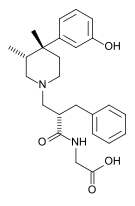

Others

Structures

| Other phenylpiperidines | |||

|---|---|---|---|

Alvimopan Alvimopan |

Loperamide Loperamide |

LS-115509 LS-115509 |

Picenadol Picenadol |